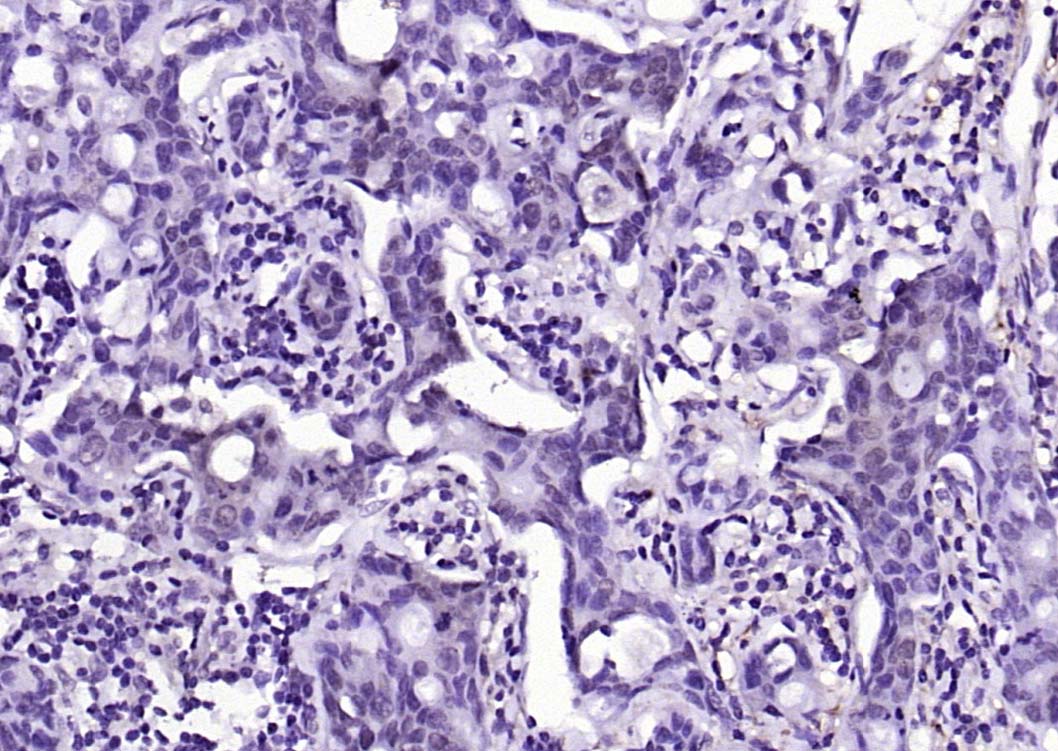

Paraformaldehyde-fixed, paraffin embedded (human brain); Antigen retrieval by boiling in sodium citrate buffer (pH6.0) for 15min; Block endogenous peroxidase by 3% hydrogen peroxide for 20 minutes; Blocking buffer (normal goat serum) at 37°C for 30min; Antibody incubation with (phospho-AKT1(Ser124)) Polyclonal Antibody, Unconjugated (bs-2849R) at 1:200 overnight at 4°C, followed by operating according to SP Kit(Rabbit) (sp-0023) instructionsand DAB staining.

Paraformaldehyde-fixed, paraffin embedded (human gastric carcinoma); Antigen retrieval by boiling in sodium citrate buffer (pH6.0) for 15min; Block endogenous peroxidase by 3% hydrogen peroxide for 20 minutes; Blocking buffer (normal goat serum) at 37°C for 30min; Antibody incubation with (phospho-AKT1(Ser124)) Polyclonal Antibody, Unconjugated (bs-2849R) at 1:200 overnight at 4°C, followed by operating according to SP Kit(Rabbit) (sp-0023) instructionsand DAB staining.

Paraformaldehyde-fixed, paraffin embedded (human breast carcinoma); Antigen retrieval by boiling in sodium citrate buffer (pH6.0) for 15min; Block endogenous peroxidase by 3% hydrogen peroxide for 20 minutes; Blocking buffer (normal goat serum) at 37°C for 30min; Antibody incubation with (phospho-AKT1(Ser124)) Polyclonal Antibody, Unconjugated (bs-2849R) at 1:200 overnight at 4°C, followed by operating according to SP Kit(Rabbit) (sp-0023) instructionsand DAB staining.